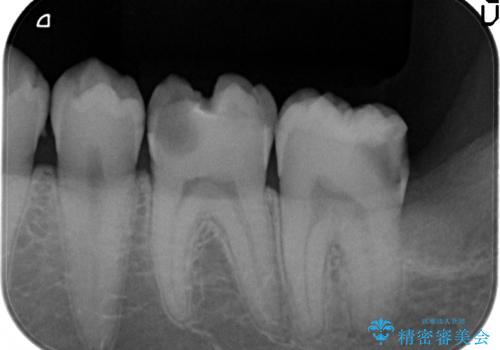

放置した虫歯の治療 親知らずの手前が虫歯

- 詰め物が取れて放置していたとのこと。

虫歯が大きかったため、被せ物(クラウン)としました。

親知らずを抜いてから治療しています。

幸い神経を取らずにすみました。